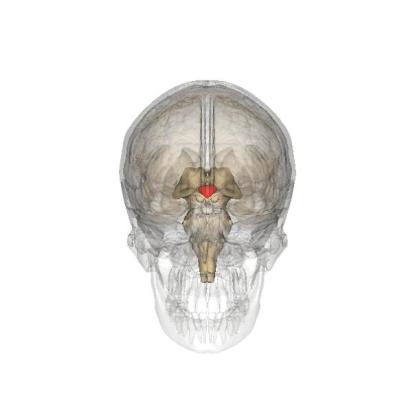

科学家们发现,当人体长期处在低温环境中,体内更容易产生棕色脂肪;当人体长期暴露在炎热环境中,则更不容易产生棕色脂肪。所以和秋天比,春天时我们的身体里有更多的棕色脂肪,也就是有更多“好燃料”。这也能解释,为什么同样是10度,我们在春天会觉得更暖和。

研究人员让男子每晚在不同温度中入睡,A第一个月24度,B第二个月19度,C第三个月24度,D第四个月27度,发现棕色脂肪数量(红色阴影)发生变化|图源:参考资料4